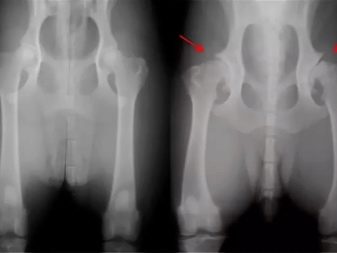

1. Hip dysplasia. In order to minimize the risk of such a disease, it is worth not physically loading the puppy at a young age. If the baby is staggering, limping and at the same time is in a sluggish state, then this may be a sign of joint dysplasia. If the diagnosis is confirmed, the veterinarian should prescribe medication or surgery.